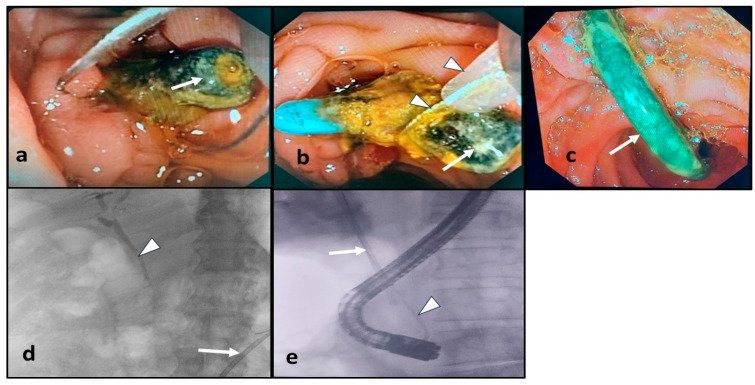

The endoscopic procedures were performed under deep sedation using intravenous midazolam and propofol. Some patients received intravenous hyoscine N-butylbromide to minimize intestinal perstalsis. All ERCP procedures were carried out using video duodenoscopes (Olympus TJF-Q180V, Tokyo, Japan and Fujifilm ED-530XT, Tokyo, Japan) by experienced endoscopists under fluoroscopic guidance. The therapeutic ERCP procedures were performed as standard of care following guideline recommendations, as follows: Biliary plastic stents in situ were retrieved using a snare or grasper. Proximally migrated biliary stents were pulled down using an extraction balloon or Dormia basket placed over the guidewire, which was advanced alongside the stent. Another technique for stent retrieval was grasping its distal end using a snare or grasper and directly pulling it out. Distally migrated biliary stents were retrieved using a snare or grasper when they were accessible. Inaccessible stents were followed up with abdominal X-ray. For patients with detected CBD stones, their removal was attempted using an extraction balloon or Dormia basket after extending the prior sphincterotomy and/or sphincteroplasty when required. Mechanical lithotripsy was used in the case of difficult stone extraction. If stone removal was incomplete, new plastic stents were inserted [ref. 8]. The endoscopic management of the forgotten-biliary-plastic-stent-related complications is demonstrated in Figure 1.

The flow chart revealed stent in situ (39 patients, 78%), distal stent migration (9 patients, 18%), and proximal stent migration (2 patients, 4%). Forty-four stents were retrieved (39 stents in situ, 3 accessible distally migrated stents, and 2 proximally migrated stents), and all of them were found to be clogged. Among these 44 patients, 23 patients had stent exchange, and 21 patients had CBD clearance. Furthermore, CBD clearance was achieved in the remaining 6 patients with distal stent migration (5 with undetected stents and 1 with an inaccessible stent) as illustrated in Figure 2.